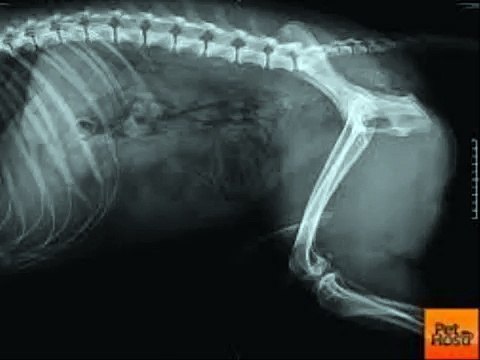

Dog Food Secrets - How Dog Bone Cancer is Diagnosed